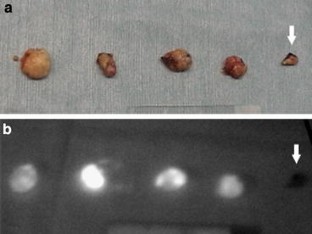

Immediately after intraoperative ICG injection, the fluorescence imaging system allowed easy visualization of the lymphatic vessels draining from the primary gastric tumor toward the lymph nodes and tracing of the moving injected dye. Some lymph vessels and nodes were hardly recognized by ICG green color or IR imaging. The ICG fluorescence system also allowed visualization of the lymph node when ICG was injected the day before surgery, similar to the radio-guided method.

Fig. 1

Fig. 2